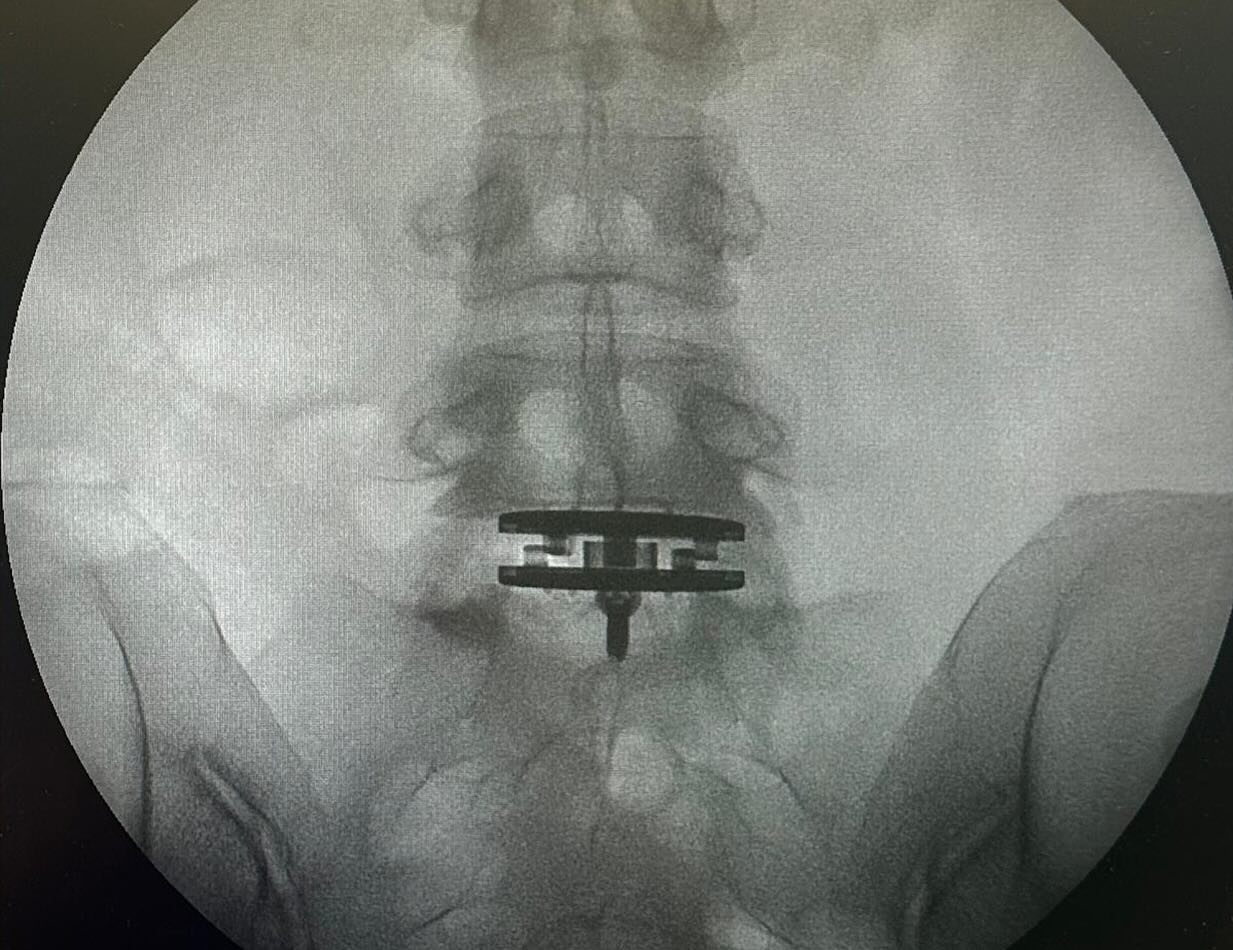

一向熱愛運動,有「肯雅徐」封號嘅徐濠縈,不時喺社交平台分享上山下海嘅運動相,但係近日佢就分享咗兩張腰椎嘅X光相,另外仲有喺手術室嘅環境相同寫有「加油!媽媽」等相關相片。

阿徐亦喺帖文以英文寫上自己情況,佢透露自己由於腰椎間盤突出問題,多年嚟一直患有背痛。喺2022年時,佢接受咗手術切除剩餘嘅椎間盤,但係下背部疼痛仍然存在。

作為一個非常活躍嘅人,佢話自己過去嘅兩年特別具有挑戰性,因為不得不停止重量訓練,喺野外滑雪,由於要攜帶沉重裝備,佢經歷過背部疼痛。呢種情況影響咗佢日常生活,每當打噴嚏時都會感到劇烈疼痛。結果喺醫生建議下,佢決定進行椎間盤置換手術。